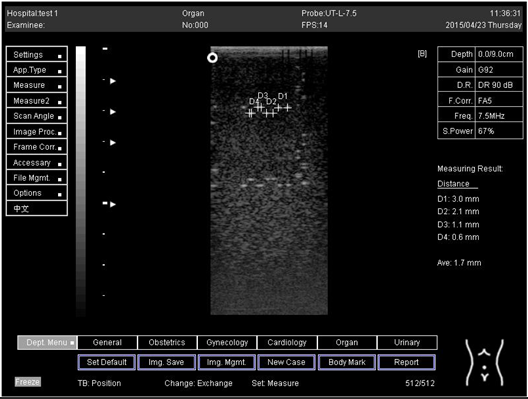

9.0 Axial resolution

Biomimetics 07 00130 i009

D1 = 5.0

D2 = 3.9

D3 = 3.0

D4 = 2.2

Lateral resolution

Biomimetics 07 00130 i010

D1 = 4.9

D2 = 4.1

D3 = 2.9

D4 = 2.0